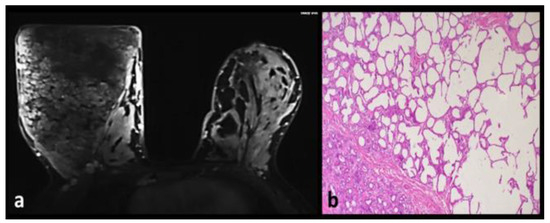

Angiolipoma